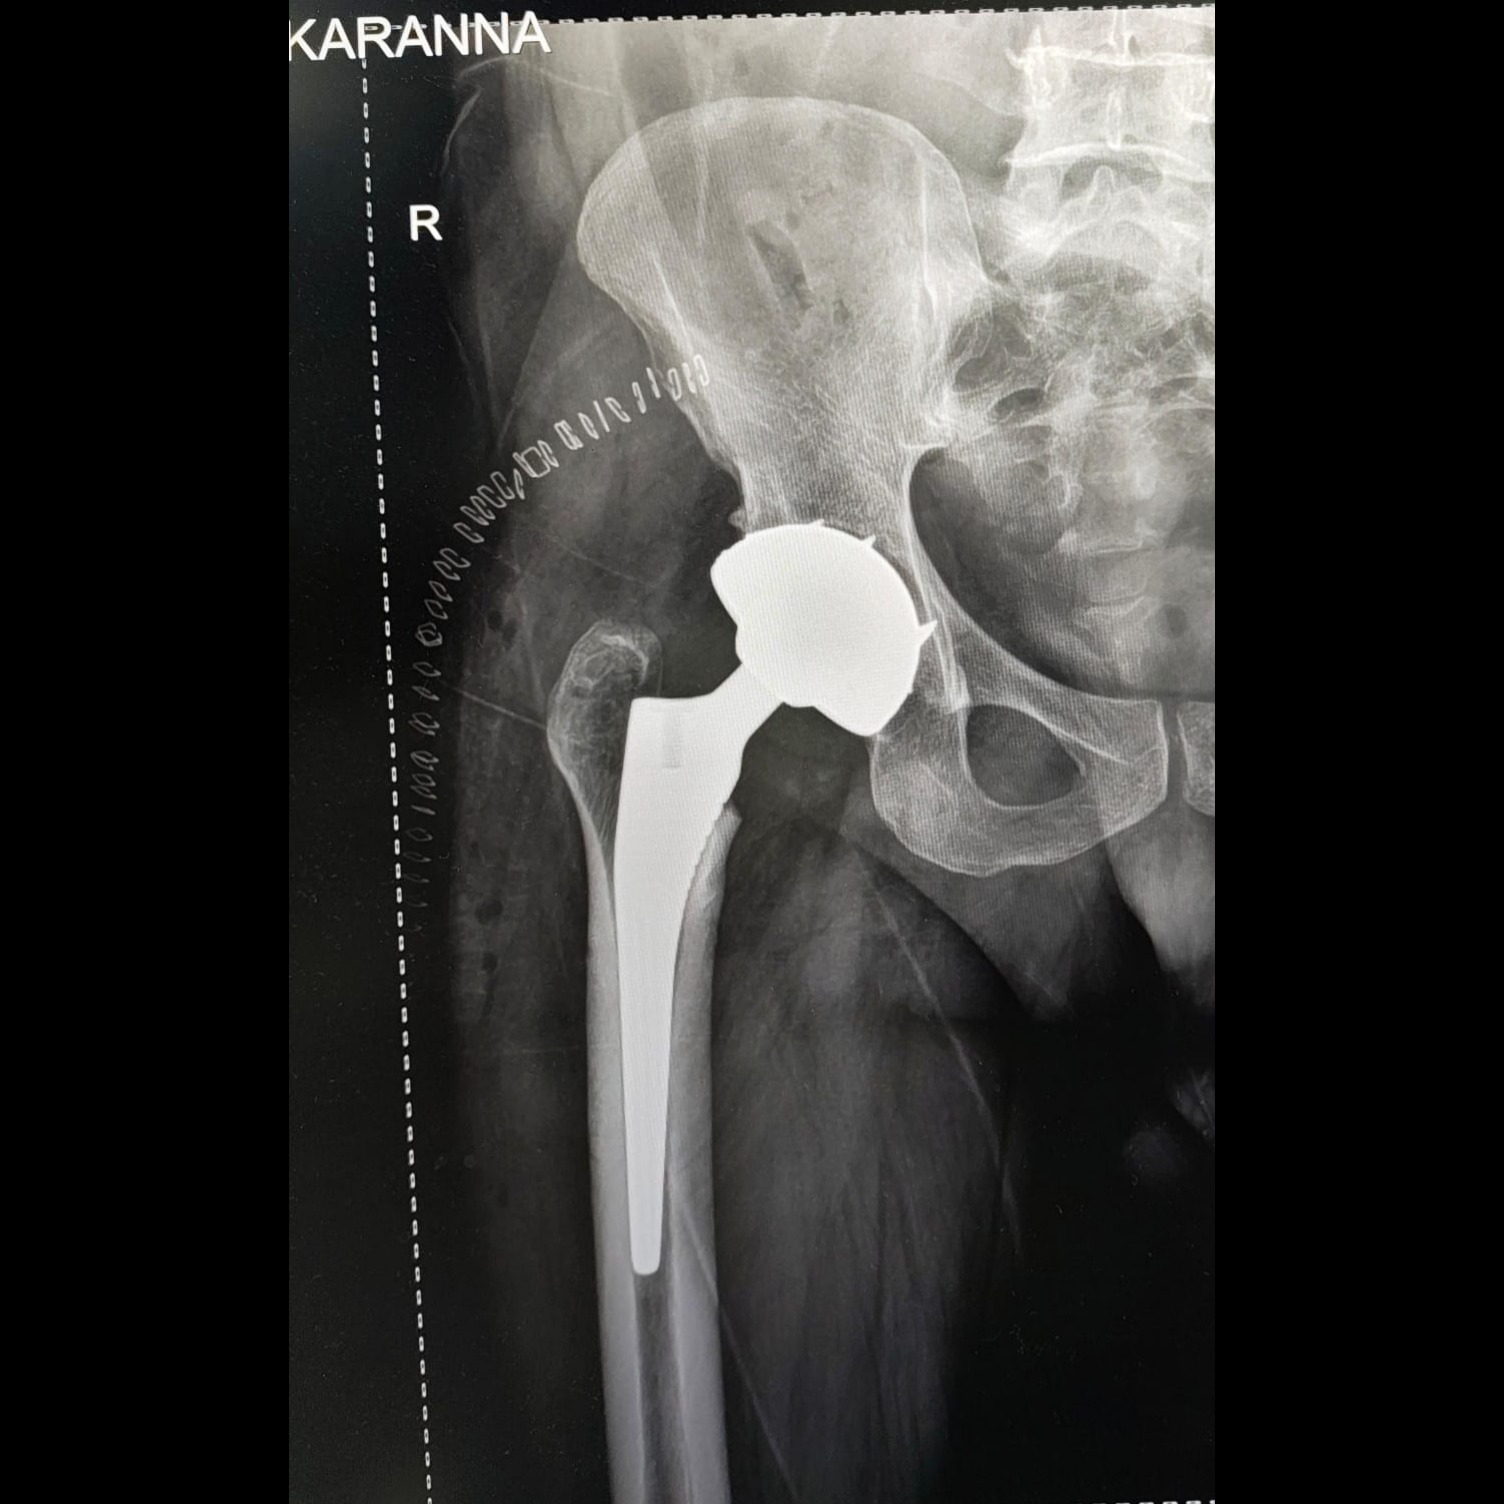

Primary Hip Replacement in Bangalore – Rediscover Pain-Free Living

Severe hip pain can limit movement and independence. SHIVAM ADVANCED ORTHO CARE Bangalore offers advanced primary hip replacement surgery to restore comfort, mobility, and confidence. The procedure replaces the damaged hip joint with a prosthetic implant, allowing smoother, pain-free motion and better joint stability. Primary hip replacement is often recommended for patients with arthritis, fractures, or joint degeneration. The experienced team ensures precise alignment of the implant to match each patient's anatomy, ensuring optimal balance and movement. Modern surgical techniques and durable implants make recovery quicker and more comfortable. Post-operative care includes physiotherapy sessions that improve flexibility, muscle strength, and joint function. Patients can usually resume light daily activities within weeks, enjoying long-term pain relief and improved posture. With personalized treatment plans and advanced medical support, SHIVAM ADVANCED ORTHO CARE remains a trusted name in orthopaedic care. If hip pain is restricting your movement, consult DR.AMARDEEP AT SHIVAM ADVANCED ORTHO CARE Bangalore today for a safe and effective hip replacement solution